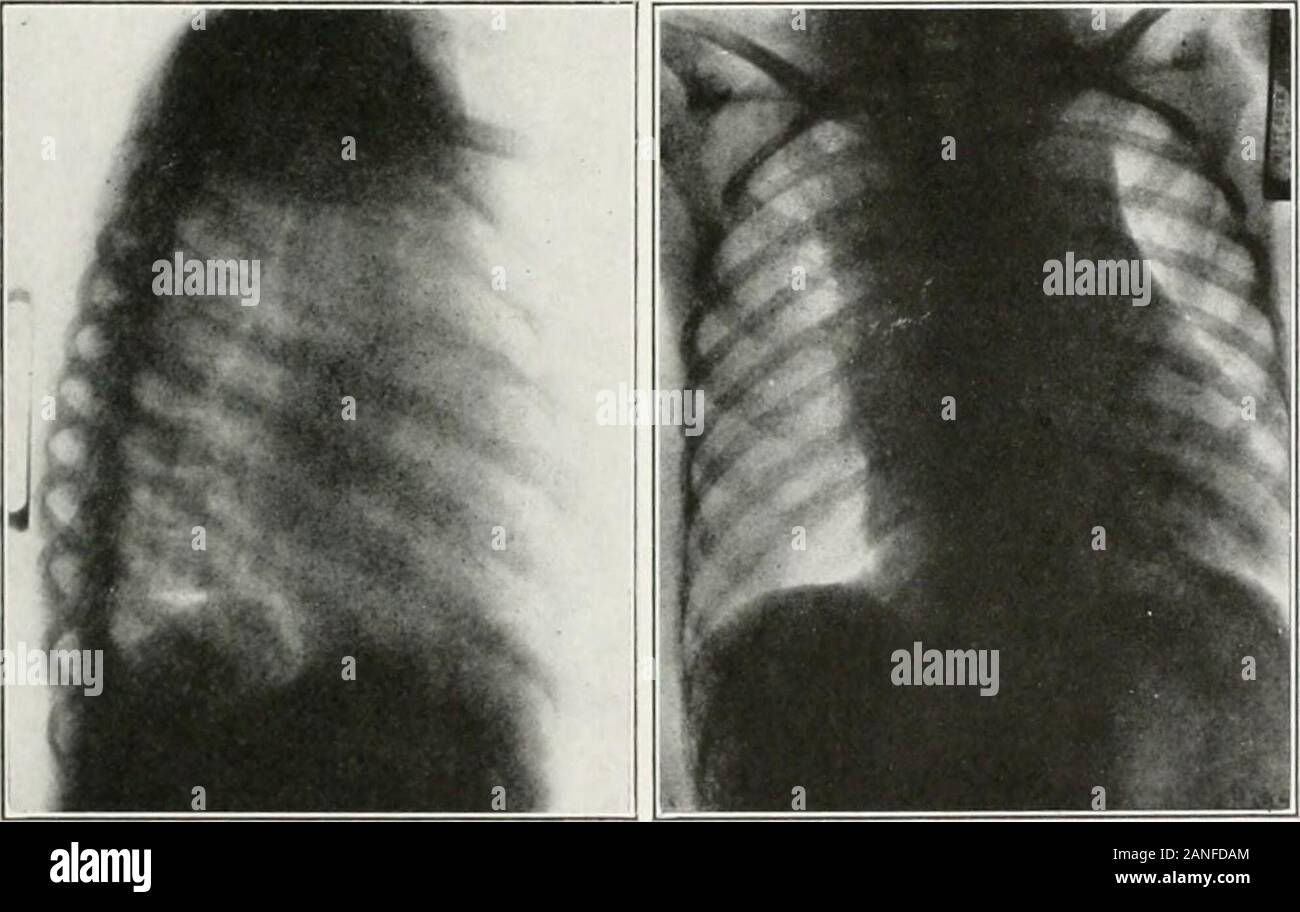

Images of posttracheotomy and postintubation long tracheal stenosis Tracheal Stenosis And Swallowing Vocal cord paralysis, external tracheal compression, radiotherapy and idiopathic subglottic stenosis (nouraei et al, 2007). Learn about the common causes, such as trauma,. This article reviews the presentation, diagnosis, and management of subglottic and tracheal stenosis (sgs/ts) caused by nontraumatic and. Acquired laryngotracheal stenosis (lts) is a rare condition causing dyspnea and stridor. Airway reconstruction for laryngo tracheal stenosis (lts). Tracheal Stenosis And Swallowing.